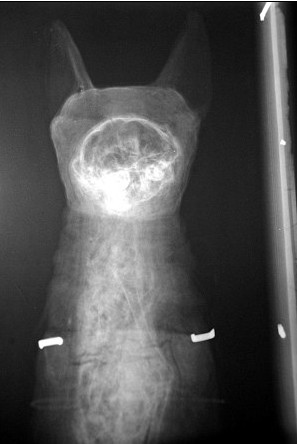

X光成像清楚地顯示出這具埃及貓咪木乃伊的臉部、耳朵、脊椎和大腦。

康沃爾郡皇家博物館的專家已經(jīng)對其進行了檢查,證實了格雷的發(fā)現(xiàn)。這家博物館的館長簡?馬利說:“我看到它非常興奮,它的臉那么可愛,包裹如此完美,是一具保存非常完好的貓咪木乃伊。”

格雷發(fā)現(xiàn)的這具貓咪木乃伊的頸部是完整的,這表明它生前是一只珍貴的寵物,并非用于祭祀的供品。目前,已有人愿意出數(shù)千英鎊來購買它,不過格雷表示自己更愿意把它贈送給博物館。